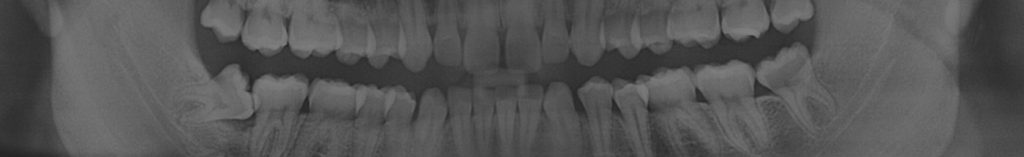

Ortopantomografía

Una ortopantomografía es una radiografía panorámica que muestra la totalidad de las estructuras orales y que se realiza en un aparato específico, denominado ortopantomógrafo. Esta técnica, realizada en Ezedent Smile Designers, permite el estudio simultáneo y comparativo de ambas articulaciones, las ramas ascendentes, los senos maxilares y la totalidad de las arcadas alvéolo dentales.

La ortopantomografía está indicada en una gran cantidad de situaciones en patología oral y maxilofacial. Es una herramienta de diagnóstico de primer orden.